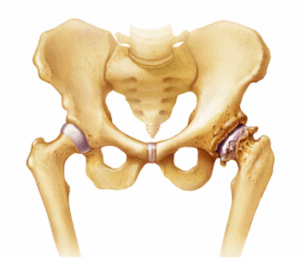

Osteophytes (Bone Spurs)

Bone spurs are bony growths that form along bone edges. They're also called osteophytes. Bone spurs often form where bones meet each other — in the joints. They also can form on the bones of the spine.